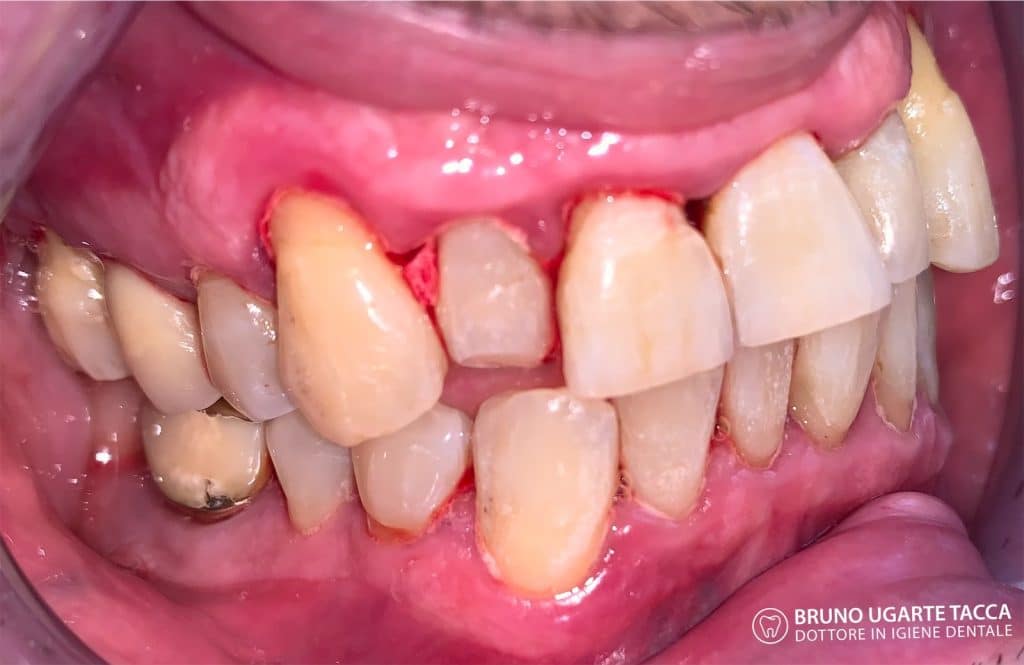

consecutive. The original protocol also includes antiseptic therapy with

chlorhexidine performed in the chair immediately after the instrumentation as well

composed:

• brushing of the back of the tongue for 1 minute with a 1% CHX gel;

• rinsing twice for 1 minute with a 0.2% CHX solution;

• spray the tonsils 4 times with a 0.2% CHX solution;

• subgingival irrigation 3 times with 1% CHX gel (repeated after 8

days).